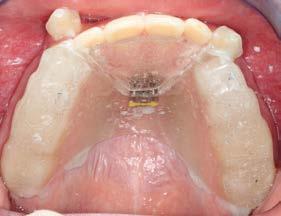

Figura 4. Colocación de expansor en forma de abanico. Figura 5. Fotografías y radiografías posplaca de expansión en forma de abanico.

En la radiografía lateral de cráneo mediante la cefalometría de Steiner podemos observar que es un paciente con crecimiento horizontal ya que presenta un ángulo Go-Gn / SN de 28°, un ANB de -4°, podemos observar que el SNA está reducido, lo que nos da el efecto de un maxilar retraído (Figura 4).

Para lograr la corrección de la mordida cruzada mediante el uso de un aparato ortopédico, se colocó una placa de expansión en forma de abanico con apoyo oclusal, el cual fue cementado con ionómero de vidrio (Multi-Cure Glass Ionomer Band Cement. Ionómero Unitek™), para así obtener un aumento de la dimensión vertical y darnos espacio para deslizar hacia vestibular el sector anterior. Se indicó activar el aparato 1/4 de vuelta al día, 2 veces por semana (miércoles y domingos) por un periodo de 2 meses y medio (Figura 5). Obteniendo como resultado cambios craneofaciales debido a una rotación horaria de la mandíbula (Figura 9).